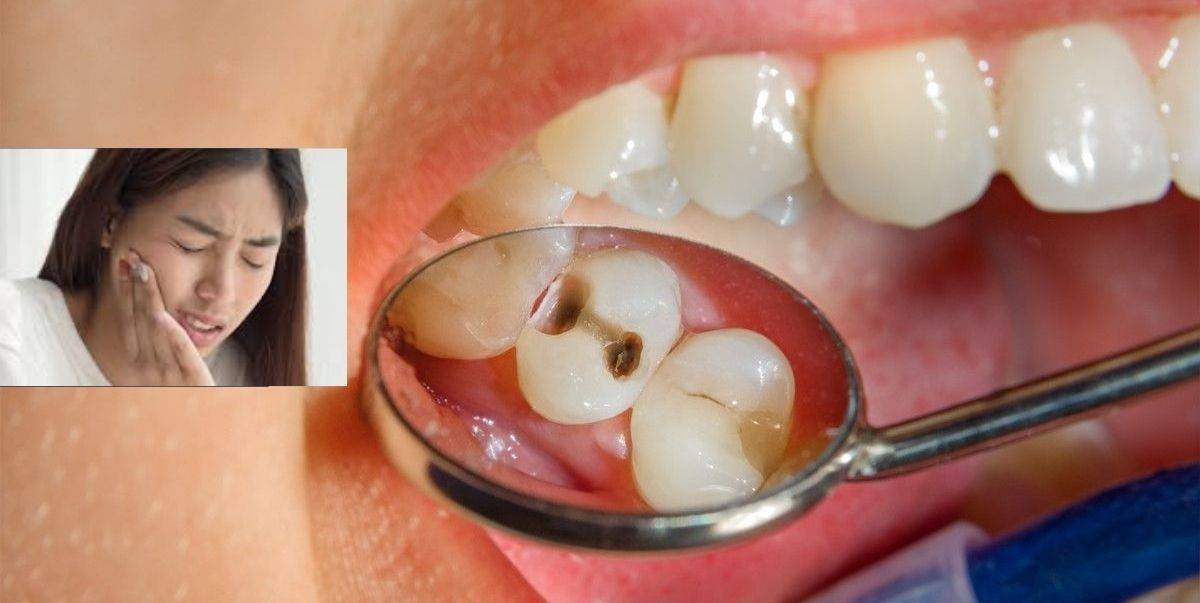

. Kandungan gula yang berlebihan dalam makanan atau minuman akan menyebabkan gigi rosak. Punca Gigi Berlubang Gigi berlubang selalu terjadi akibat daripada kurang penjagaan gigi dan kebersihan mulut. Menurut Doktor Verde Putra gigi berlubang besar tapi tidak sakit masih perlu meendapatkan rawatan daripada doktor gigi.

Sakit pada gigi bisa disebabkan oleh banyak hal. Gigi berlubang atau tambalan gigi yang rusak Gigi atau gusi yang meradang atau infeksi Gigi retak atau patah Gigi membusuk Gigi tanggal atau copot Gigi sensitif Proses tumbuh gigi Gigi bungsu yang tumbuh tidak normal impaksi gigi Nanah di gigi Gusi bengkak. Sakit gigi akibat masalah di dalam rongga mulut dapat disebabkan oleh.

Terang Dr Rahimah karies adalah penyakit gigi yang apabila tidak dikawal akan menimbulkan kerosakan atau kereputan gigi yang meninggalkan kesan sebagai satu kaviti atau lubang. Caranya adalah seperti berikut. Tidak adanya rasa sakit di awal membuatmu tidak sadar dengan masalah gigi ini.

Ini adalah gealan kerusakan yang terletak di jaringan keras gigi. Namun di antara semua ini penyebab utamanya adalah karena kurang menjaga kebersihan dan merawat gigi. Penyebab lainnya dapat berupa penyakit sinusitis gangguan saraf pada wajah.